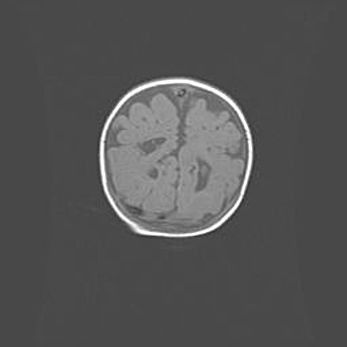

Множественные кисты обоих полушарий головного мозга, наибольшая из них в правой затылочной области. Ассиметричная атрофическая гидроцефалия.

Возраст: 7 месяцев

Вес: 5660 г

Пол: мужской

Окружность головы: 41,5 см

Срок гестации: 28-29 недель

Кисты головного мозга развиваются в результате многоочаговых некрозов вещества мозга и возникают вследствие перенесенной перинатальной инфекции, менингитов, энцефалитов, асфиксии, родовой травмы, расстройств мозгового кровообращения различного генеза. Образованию кист в веществе головного мозга плодов и новорожденных способствуют такие факторы, как высокое содержание в нем воды, недостаточная (или отсутствие) миелинизация и слабая астроглиальная реакция на повреждение.

Кисты могут сочетаться с гидроцефалией и другими поражениями головного мозга.